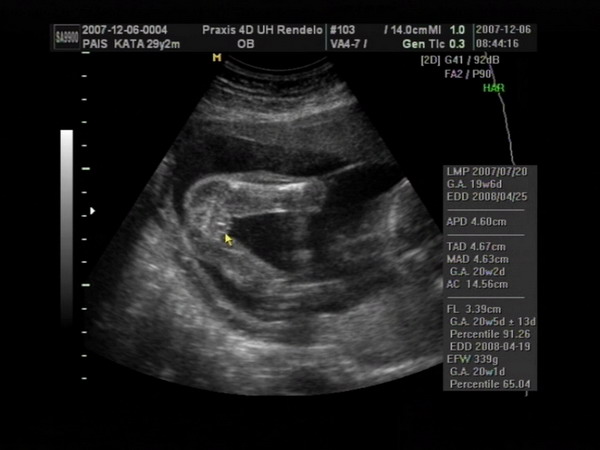

Végre sikerült olyan formátumot csinálni a 4D-s képeinkből, amit ide is fel tudok tenni, úgyhogy büszkén fel is teszem a fotókat :).

Csenge nagyon fotogén volt:

Kép

Marci megpróbált elbújni a medencecsontom mögé, mert a tesója állandóan az ő vállaira akarta feltenni a lábait - ráadásul a feje fölött volt vmi, ami árnyékot vetett a kobakjára:

Na és az egyértelmű bizonyíték arra, hogy Csenge kiscsaj:

Itt pedig a kis pöcsös látható:

Kata

Meli, elméletileg a kiscsaj van alul, és felette a kisfickó - de ez nem 100%, mert dec. 6-án voltunk 4D-n, és azóta lehet, hogy megfordultak. Tegnap voltam dokinál, ő viszont már azt mondta, hogy a végleges helyükön vannak a törpék, már nincsen helyük megfordulni (az viszont nem látszott tegnap, hogy melyik van alul-felül). Mikuláskor kb. 35 dkg-ok voltak, tegnap csak a fejüket mérte a doki bácsi. Minden rendben van velük, de harántfekvéses mindkettő :roll: